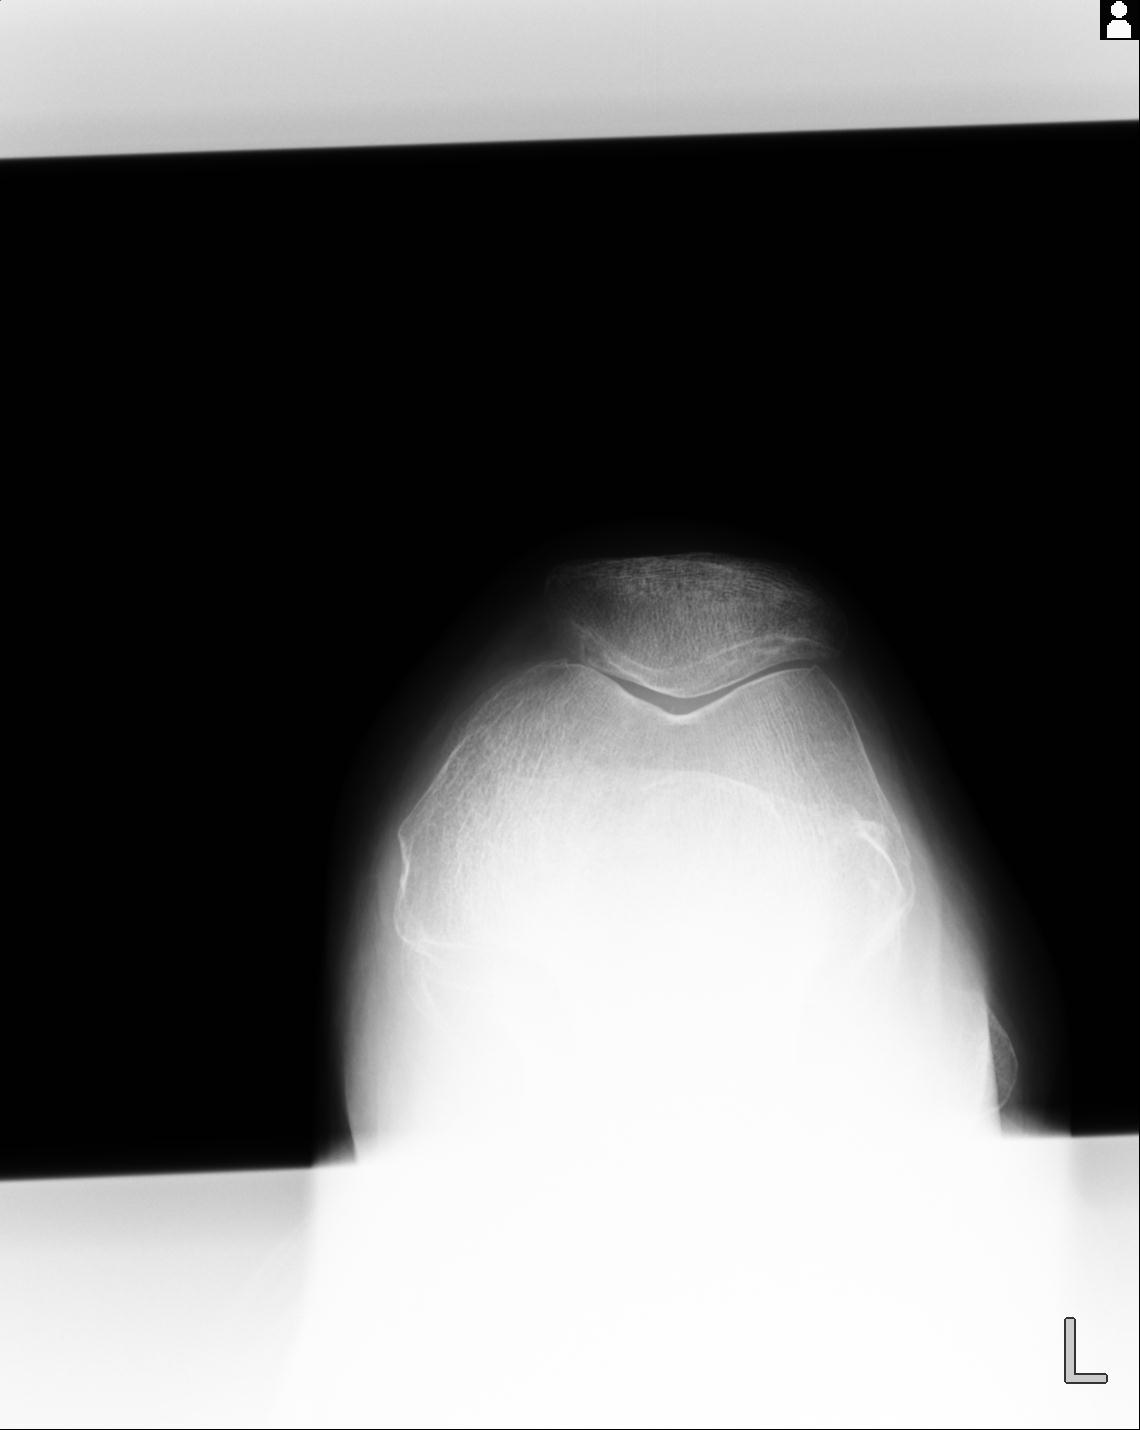

49554 3/13 膝 4R 3/16 4R 1/18 2R 78歳男性 膝蓋骨骨折